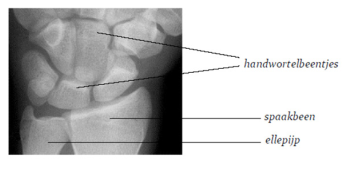

Je pols is een gewricht. Het wordt gemaakt door de botjes in je hand en de twee botten in je onderarm: je spaakbeen en je ellepijp. Bij kinderen is het bot veel soepeler dan bij volwassenen. Om het bot zit een laagje dat beenvlies heet. Bij jou is dit laagje dikker dan bij volwassenen.

Er wordt een foto van je pols gemaakt. De dokter kijkt dan of je pols gebroken is en wat voor breuk het is. Als het bot goed staat, krijg je gips om je hand en onderarm.